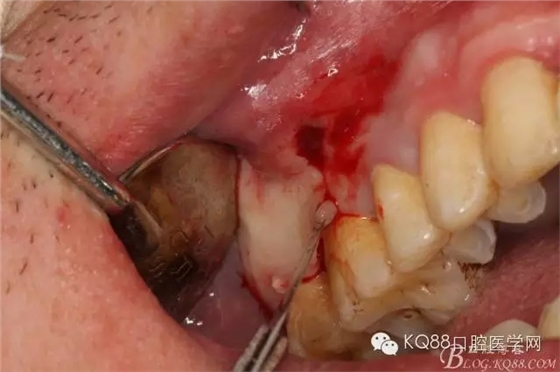

圖1.臨床檢查:16和17牙體組織正常、活力正常,其上方的前庭溝有一膿瘺,鑷子探查有大量膿性分泌物溢出。

圖6.局部浸潤麻醉下。在16的近中做垂直切口+遠(yuǎn)中齦溝內(nèi)及上頜結(jié)節(jié)水平切口

圖7.翻全厚瓣。發(fā)現(xiàn)17牙根方的骨質(zhì)破損,破損處有大量膿性血性分泌物溢出。

圖8.繼續(xù)翻瓣至上頜結(jié)節(jié)處,發(fā)現(xiàn)骨壁缺損有花生米大小,腔隙內(nèi)有大量肉芽組織。